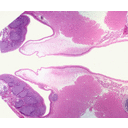

NasalCavity.jpg